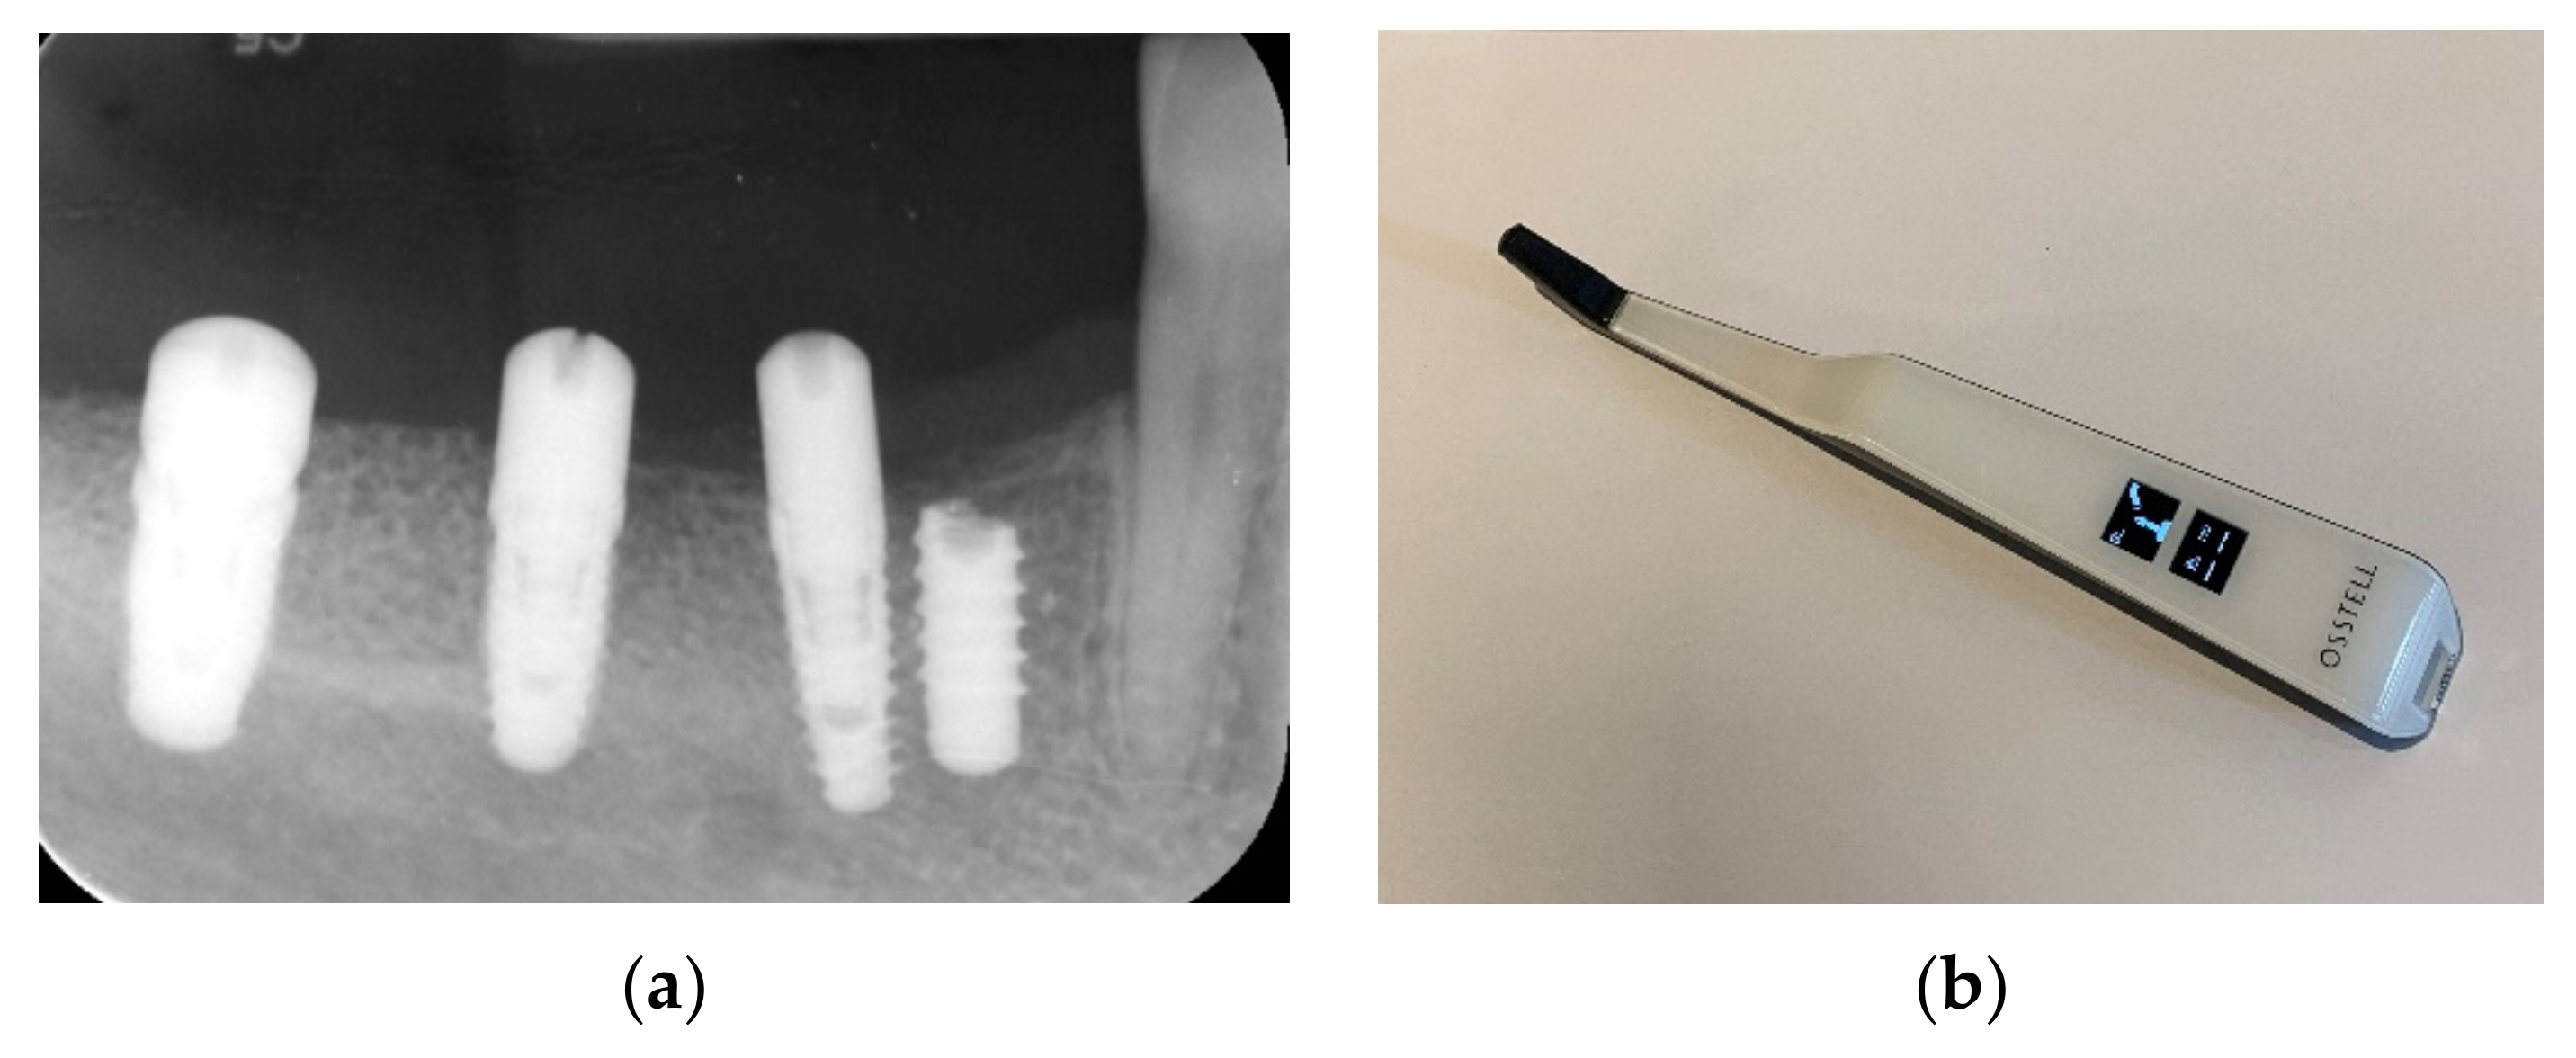

9. Prosthetic Treatment

After 3 months of osseointegration, healing abutments were placed, and the implant stability was evaluated with a resonance frequency analysis (RFA) and ISQ values utilizing the Osstell device, showing great implant stability (Table 1) (Figure 18a–d).

Table 1.

Insertion torque and ISQ values.

Figure 18.

Stability ISQ measurements (a–d).

Impressions were taken using an open impression tray. The abutments were individually designed, and the bridge was made with a zirconia structure and baked porcelain for a screw-retained cantilever bridge. The bridge was delivered and screwed on at 30–35 Ncm 4 months after implant placement (Figure 19a–c) and, in total, ten months after placement of the allograft customized bone block, showing an excellent esthetic result. Teflon tape was placed over the screws to establish retrievability. The Teflon was covered finally with a composite to improve the esthetic clinical outcome (Figure 20a,b).

Figure 19.

Prosthetic planning and design (a–c).

Figure 20.

Bridge delivery (a) and control radiograph (b).